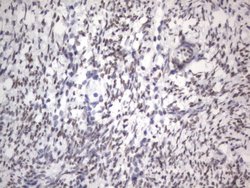

RBFOX1 Mouse anti-Human, Clone: OTI4F9, lyophilized, TrueMAB™

| Immunohistochemistry (Paraffin), Western Blot | |